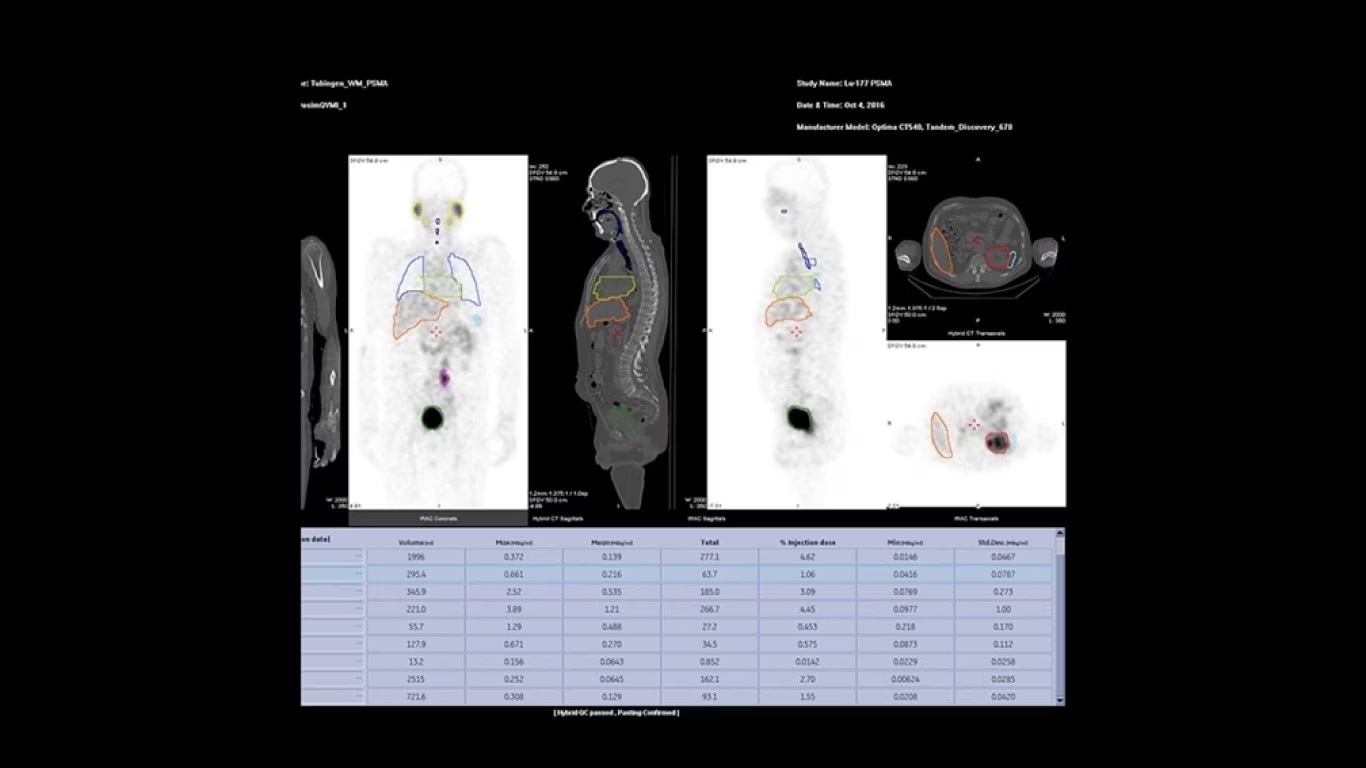

Experience a new productivity hub for hybrid imaging. By automating SPECT/CT reconstruction, SmartConsole simplifies the workflow for complex hybrid and quantitative protocols and allows technologists to review results directly at the scanner console. It also allows physicians to review scans remotely from mobile devices. They can modify processing settings and initiate study processing anytime, anywhere across a LAN or a WAN*.

SmartConsole enables a noticeable improvement in productivity. Now, a physician can provide their input remotely and digitally. For example, physicians can review a whole-body bone scan directly on their tablet or other mobile device and define the scan range limits they need from wherever they are. The time saved with this switch to a digital workflow helps make it possible to complete exams in predictable time slots.